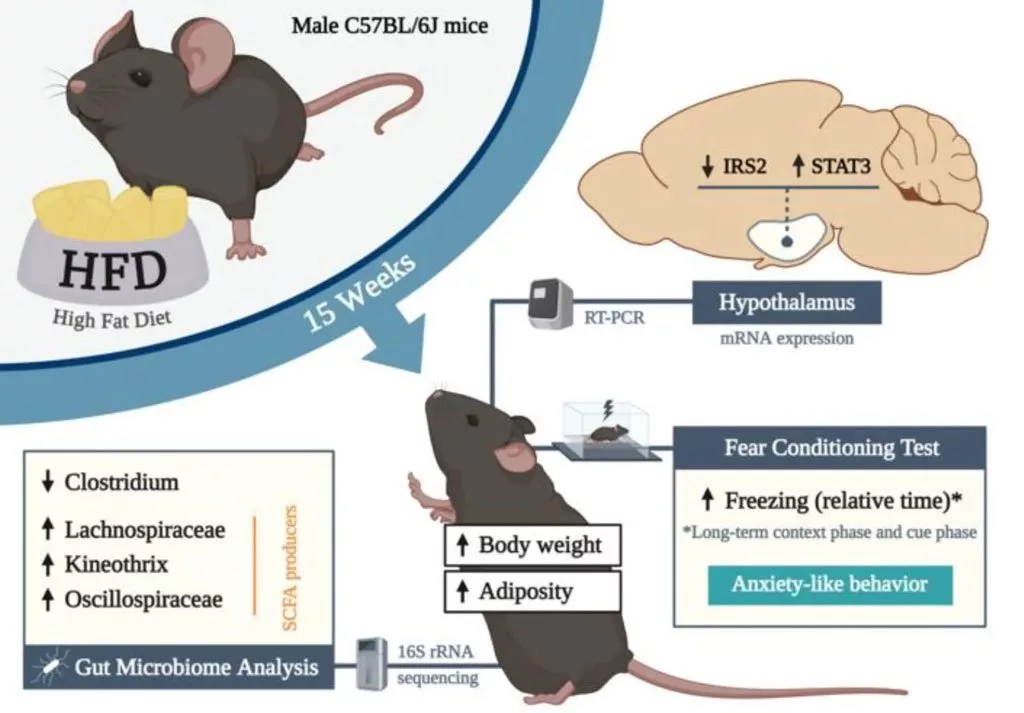

[ad_1] نوشته و ویرایش شده توسط مجله ی کویر دانش محققان بهتازگی رابطهای بین رژیم غذایی ناسالم با افت کیفیت عملکردهای شناختی را کشف کردهاند که میتواند به علائم بسیاری از جمله افزایش اضطراب، دامن بزند. چرا سلامت دستگاه گوارش…